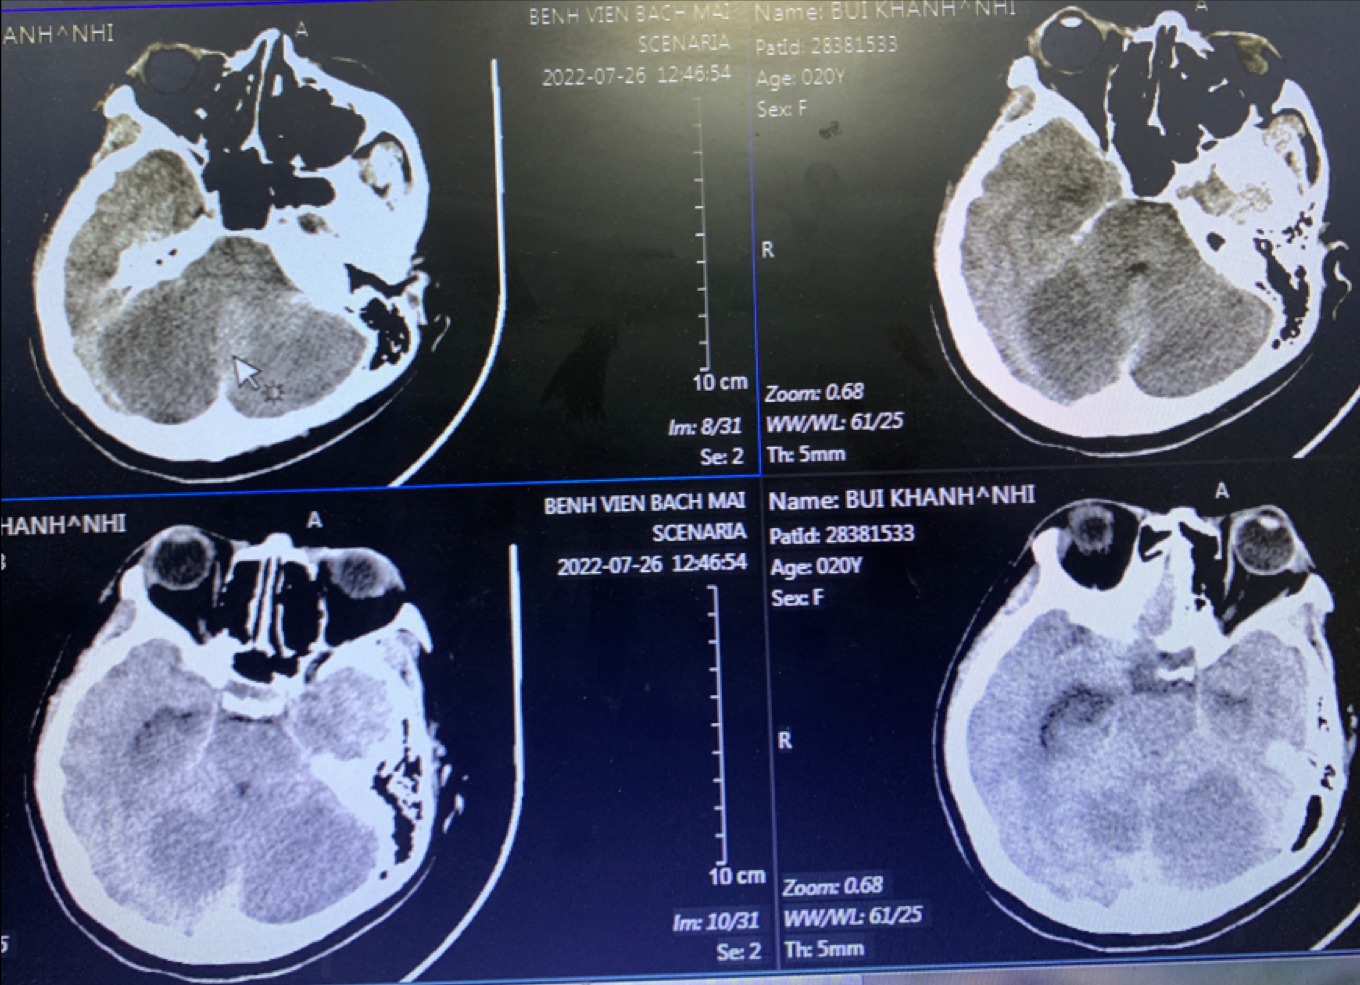

Hình ảnh não 1 bệnh nhân 17 tuổi có tổn thương sau hút thuốc lá điện tử (Ảnh: BSCC).